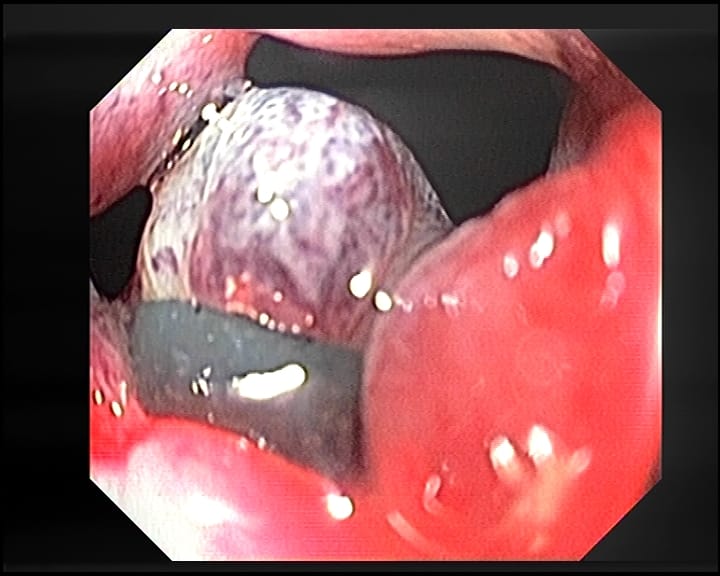

- Colocación de las Bandas: Usando el colonoscopio, se colocan pequeñas bandas de silicona alrededor de las hemorroides. Estas bandas cortan el suministro de sangre a las hemorroides, haciendo que se sequen y eventualmente se desprendan.